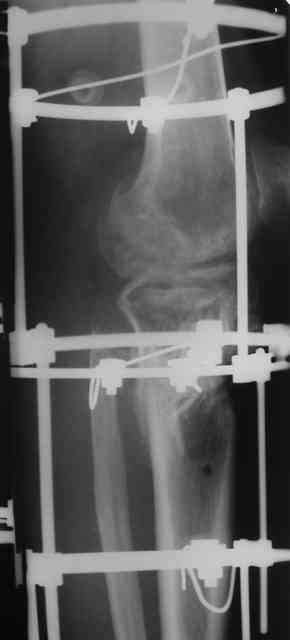

Р-граммы и фото за 4.05.2007 - 7-е сутки после операции.

Ход операции - линейным разрезом по передней поверхности голени обнажена зона ложного сустава большеберцовой кости. От кости отсепарованы медиально м/ткани. Из зоны ложного сустава убраны рубцовые ткани, мобилизован дистальный отломок. По передней поверхности удалены два осколка, связанных грануляциями. Произведено удаление грануляционной ткани из проксимального отломка (на вид сине-серого цвета), "чистого" гноя не было. Затем произведено наложение аппарата и репозиция отломков. По передне-медиальной поверхности образовался дефект до 4х2х2 см + полость в проксимальном отломке. Удаленные осколки очищены от грануляций, уложены в место дефекта, зажаты между отломками. После иссечения раны по передней поверхности, находящейся рядом с операционной раной, последняя ушита с большим натяжением.

Перелом мыщелка сросся. Проксимальный отломок очень порозный.

На перевязках - из раны небольшое кол-во сукровичного отделяемого. Отек голени умеренный, состояние кожи на фото.

Аппарат видел, репозиции не заметил. О "наложенном" аппарате: спицы в проксимальном отломке б\берцовой кости проведены очень низко, и опять только две, как и в первом аппарате. Почему только одна спица в дистальном парафрактурном кольце? Проксимальная база на бедре должна улучшить стабильность проксимального фрагмента tibia? Ничего подобного двумя спицами в одной базе при таком длинном рычаге вы не добьетесь, а вот совсем потерять движения в коленном суставе они почти гарантируют.

О репозиции: мыщелок сросся и слава Богу, но основные отломки фиксированы в вальгусном положении, собственно как и было, это критично. В чем состояла репозиция?

Кольцо с бедра демонтировать. Добавить кольцо проксимальней к коленному суставу с двумя спицами. Соединить с нижним предварительно проведя еще одну спицу в этом кольце. Получится проксимальный модуль.

Провести еще одну спицу в проксимальном кольце дистального модуля. Между ними (модулями) убрать штанги ... "через колено" устранить варус и зафиксировать тремя резьбовыми штангами.

Вы писали, что открыто "отрепонировали" отломки ... Чессслово, не увидел